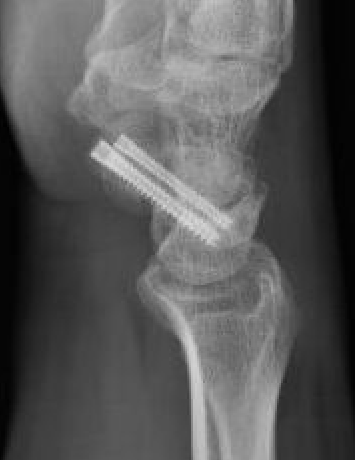

Open dorsal approach

Indications

Displaced proximal pole fractures

Proximal pole nonunion

Waist fractures

Scaphoid fracture with perilunate dislocation / scapholunate ligament repair

Technique

AO surgery foundation dorsal approach to scaphoid

Vumedi open dorsal approach to scaphoid video

Vumedi open dorsal approach 2 screw fixation proximal pole video

Dorsal approach

- incision centered on Lister's tubercle

- preserve superficial radial nerve

- open 3/4 extensor compartment

- reflect EPL radially, reflect EDC ulnarly

- open capsule

- preserve dorsal ridge vessels

Flex wrist and reduce fracture

- insert K wire

- proximal fragment into distal fragment

- entry point is just radial to SL ligament

- drive into trapezium / use additional anti-rotation K wire

- check position on multiple views

- insert headless compression screw